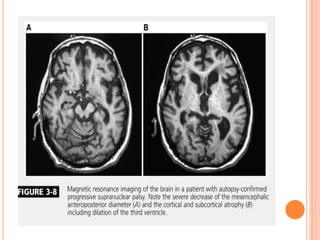

 MRI-

midbrain atrophy

Superior cerebellar peduncle atrophy.

“morning glory flower sign” and the “hummingbird sign” are

quite specific but show low sensitivity (50% and 68.4%,

respectively